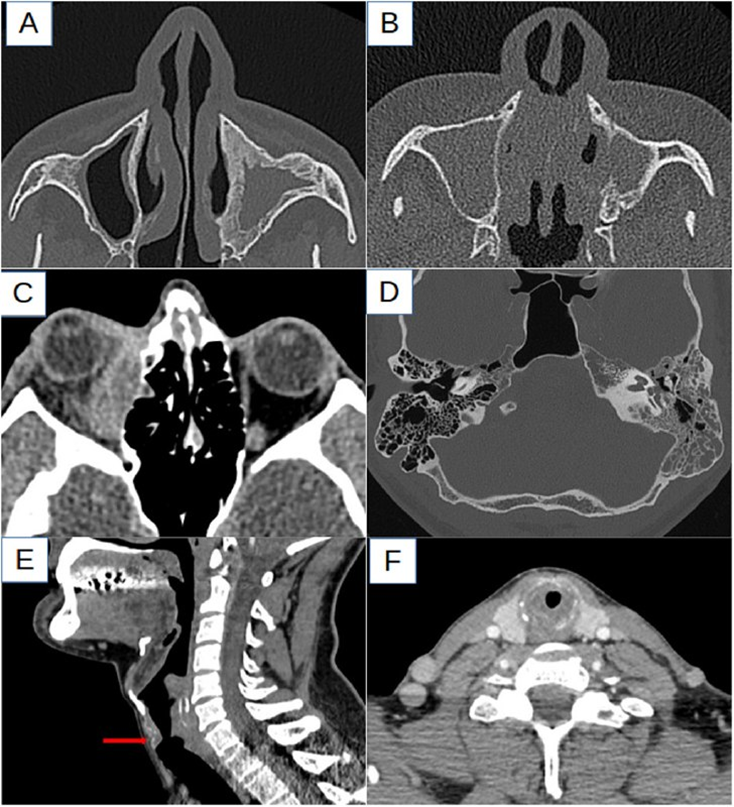

Рис.1.

А. Заполнение левой верхнечелюстной пазухи и утолщение каркаса кости, свидетельствующие о хроническом характере поражения.

B. Уменьшение объема левой верхнечелюстной пазухи и остеолиз внутренней стенки.

C. Дополнительный объем ткани в области нижнего внутреннего квадранта правой глазницы, ответственная за нарушение функции глазницы. экзофтальм.

D. Почти полное заполнение клеток левого сосцевидного отростка.

Е, F. Гомогенный тканевый голосово-подглоттический стеноз по отношению к перстнечелюстному хрящу